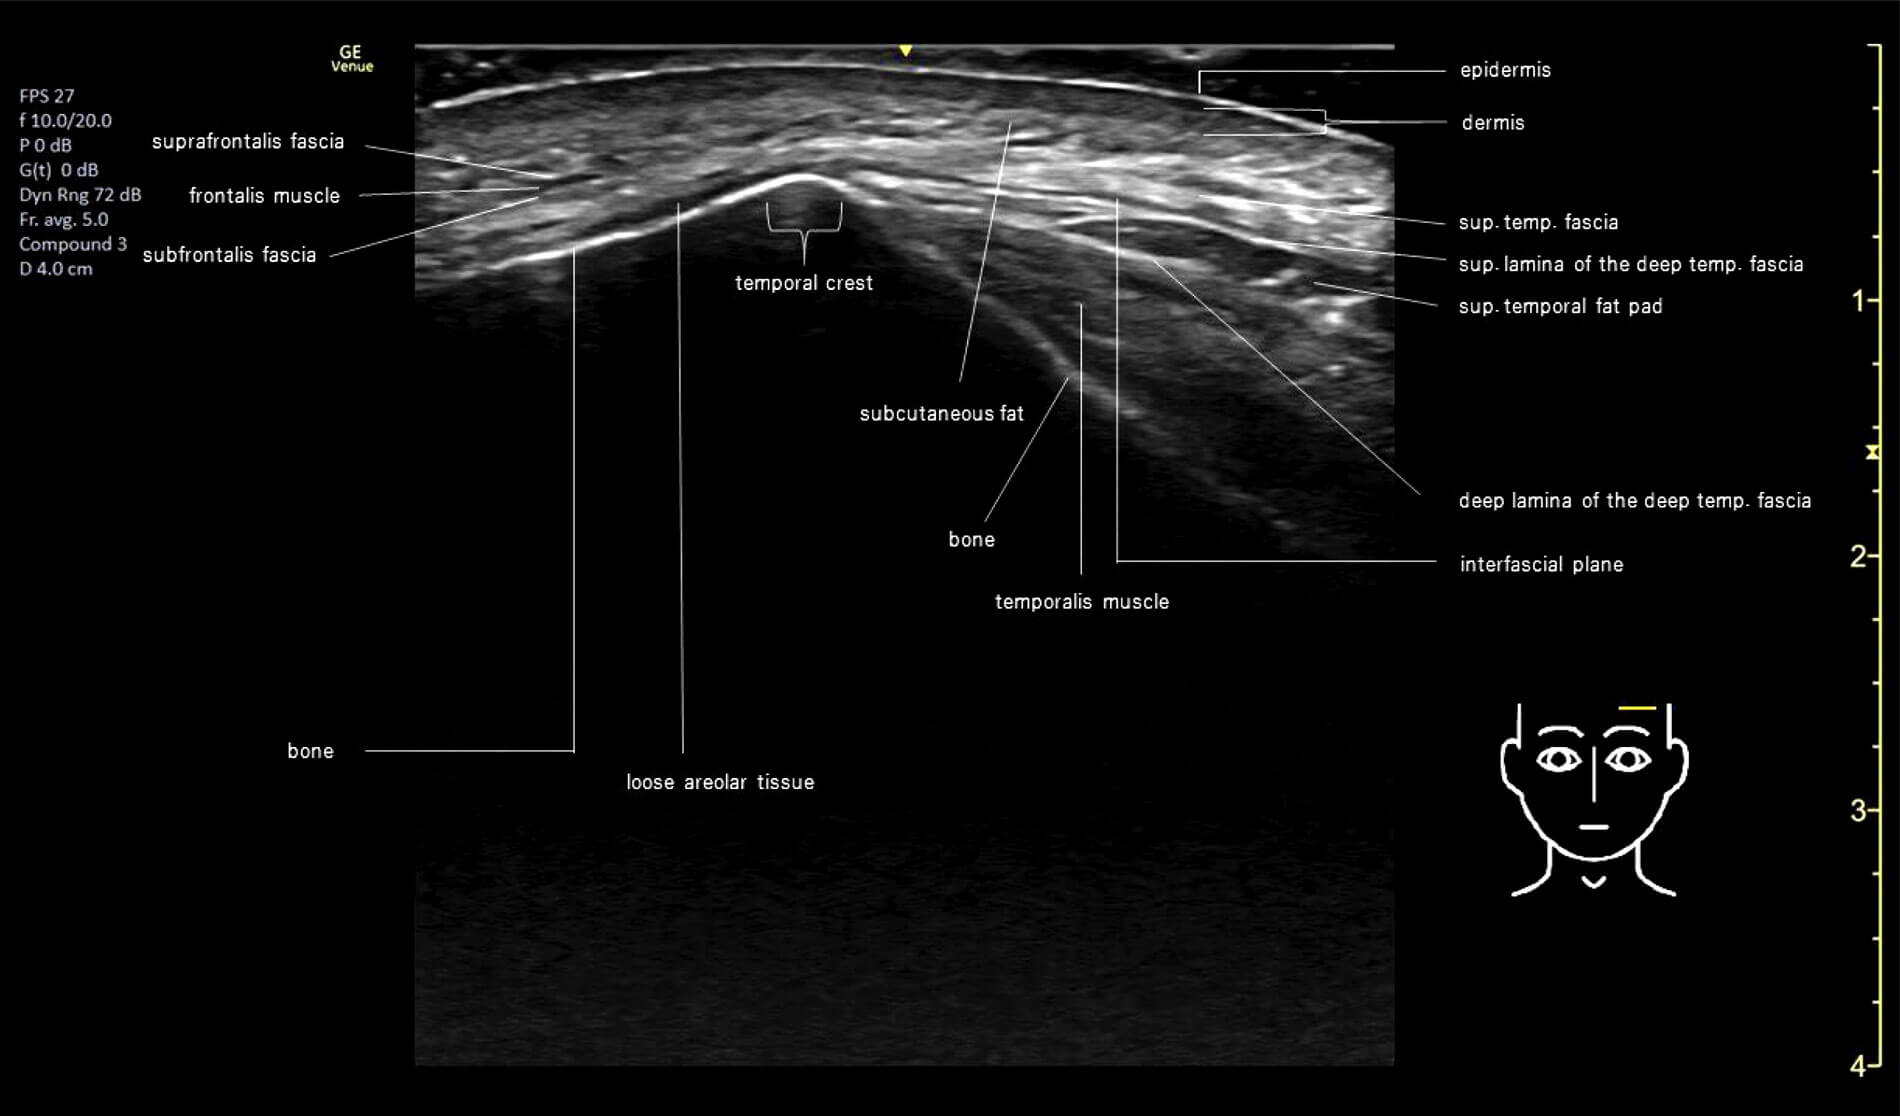

A recent study re-evaluated the anatomy of the forehead using cadaveric dissections and ultrasound imaging of live subjects, revealing a novel concept by identifying additional layers (suprafrontalis fascia, retrofrontalis fat and subfrontalis fascia) to the already recognised layered arrangement. Additionally, reinforcing the deep fat compartments or supraperiosteal plane as the preferable location for dermal filler injections to address loss of volume and contour, as nerves and arteries travel deep to the frontalis muscle but superficial to the subfrontalis fascia [4]. The temple, also referred to as the temporal fossa, has a more intricate anatomical arrangement compared to other facial areas.

Current literature shows the presence of 13 layers [5], all already described by previous cadaveric studies [6] but with a somewhat different nomenclature. The superficial temporal fascia (STF) encases the superficial temporal artery within its laminae (layers 3 and 4) and it represents the superficial musculoaponeurotic system (SMAS) in this region.

The deep temporal fascia (DTF) separates into a superficial (layer 8) and a deep layer (layer 10) before their connection to the zygomatic arch, enveloping layer 9 (superficial temporal fat pad).The deep temporal fat pad that lies under the DTF is also known as temporal extension of the buccal fat pad of Bichat. If injections are too low in the temporal fossa, the product can spread to the midface via this fatty connection.

Appreciation of this complex layered arrangement is essential when selecting the injection technique; more superficial injections with a less cohesive product are indicated for light to mild correction, and deeper delivery of the material such as in supraperiosteal for correction of moderate to severe depression of the temple require a higher G prime product. Deep injections also require a greater amount of product to fill the depression and ‘lift’ the overlying layers. A combination of techniques can provide a better clinical outcome in selected cases [7].

A Brazilian study from 2023 questioned the safety of interfascial injections after a high incidence of incorrect placement (89%) when these were performed with no image guidance in fresh frozen specimens, recommending the use of ultrasound imaging when selecting this technique [8]. A detailed ultrasound image illustrates the intricacy of this layered arrangement (Figure 2).

Figure 2: Ultrasound image of layered arrangement of forehead and temples.

Credit: Jair Mauricio Cerón Bohórquez, MD, Medical Contour, Hamburg, Germany.